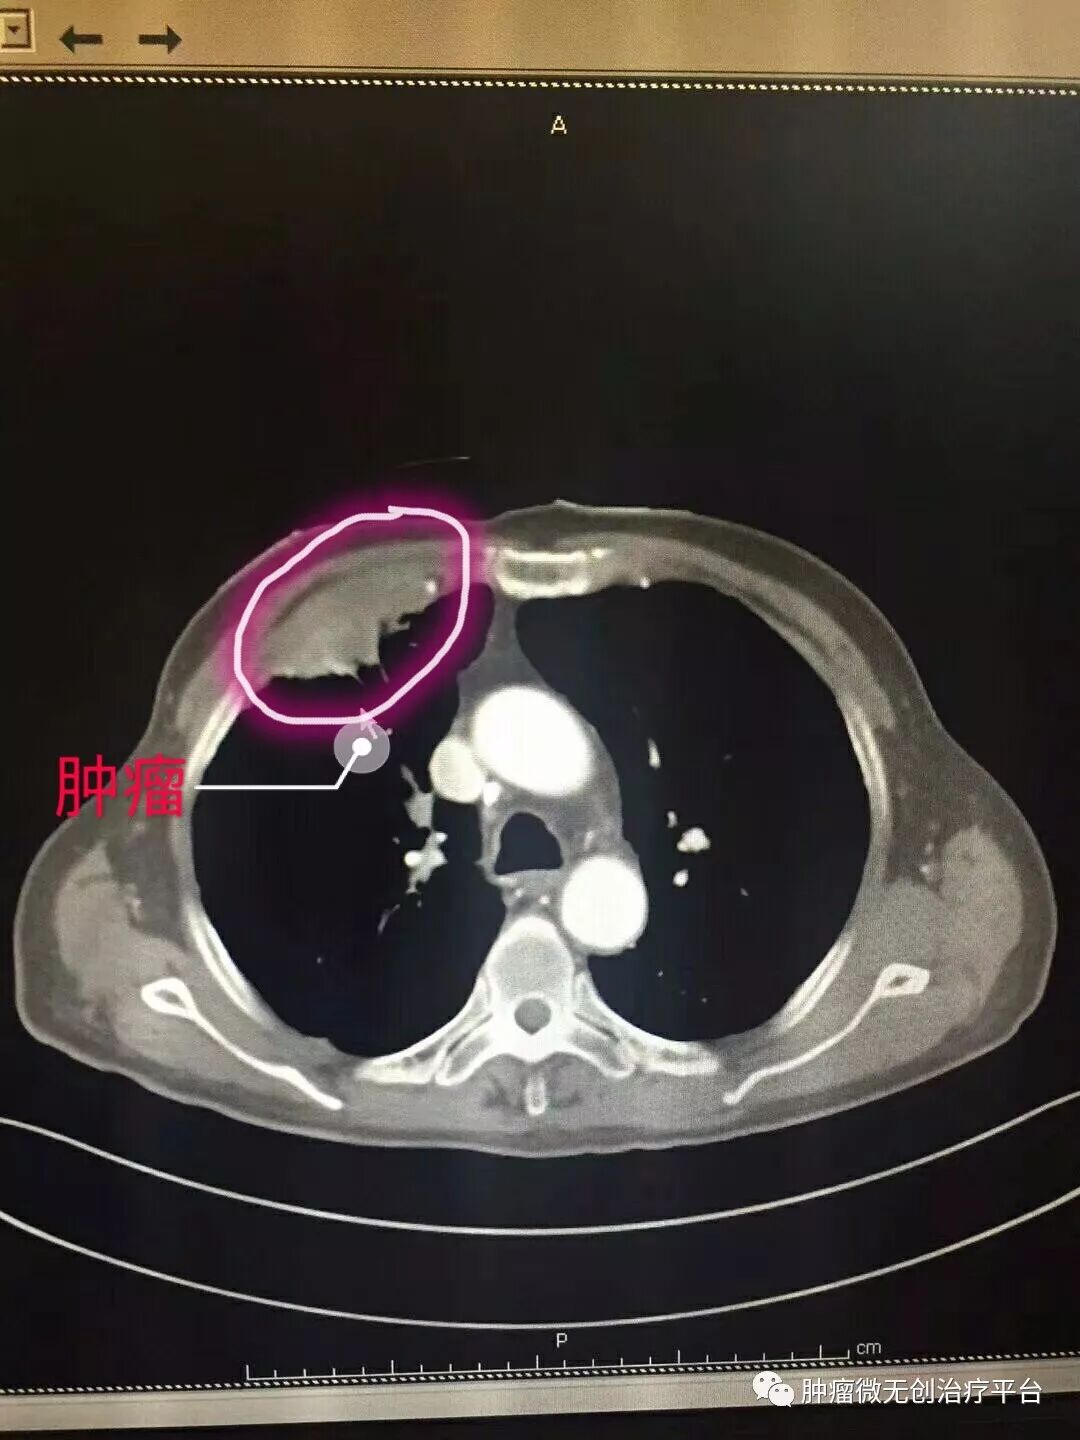

正文:5月28日,右肺腺癌侵犯胸壁患者,在天津市武清区中医医院胸外科进行氩氦刀冷冻消融治疗。

患者情况高龄(79岁)右肺腺癌侵犯胸壁患者肿瘤供血动脉栓塞➕氩氦刀冷冻消融术:图1-2术前PET-CT;图3术前CT;图4-5肿瘤供血动脉栓塞介入;图6-9氩氦刀冷冻消融治疗。